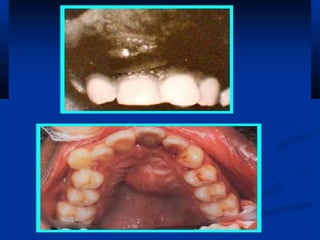

PericoronitisPericoronitis

Lower third molarLower third molar